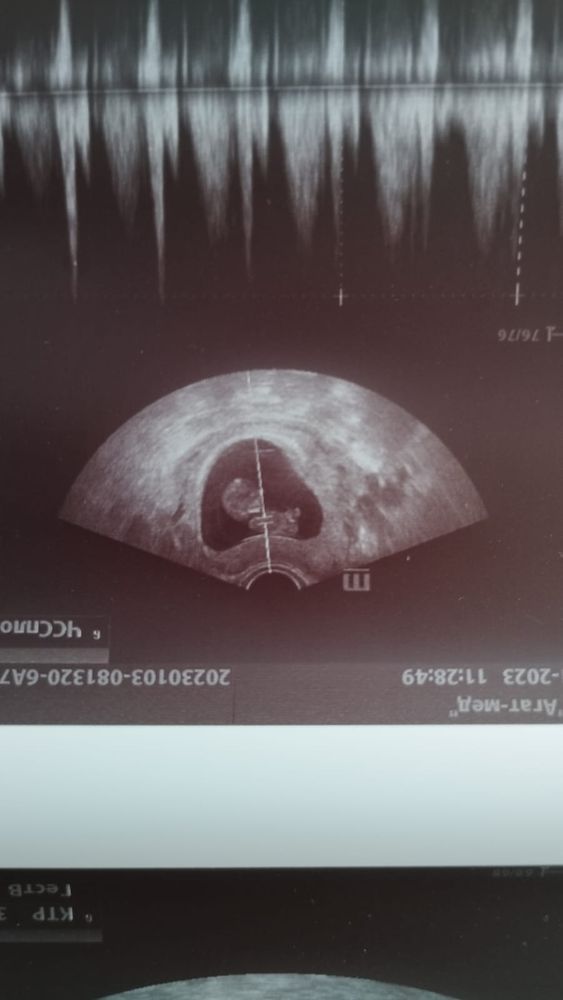

Ваши ощущения не идут в сравнение с узи. Девочка значит девочка. На вашем фото скрининга нет полового бугорка, оно бесполезное